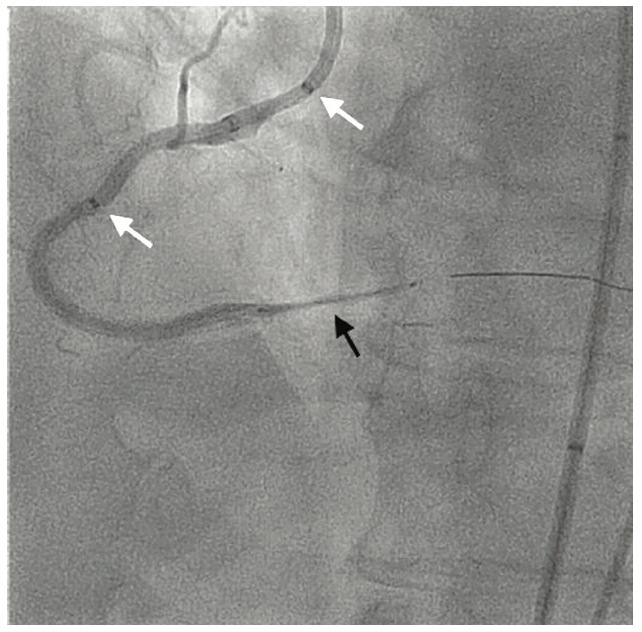

A 64-year-old male presented with a 3-week history of accelerated angina. Past medical history was significant for diabetes, hypertension, hyperlipidemia, obesity, and coronary artery disease. Previously he had PCI of the proximal, mid, and distal right coronary artery (RCA). Cardiovascular examination was unremarkable. Coronary angiography revealed an instent chronic total occlusion (CTO) of the proximal RCA (Figure 1). Antianginal medications were optimized according to clinical practice guidelines; however, the patient continued to have persistent symptoms. Myocardial perfusion imaging revealed a large-sized area of severe ischemia involving the inferior wall. Echocardiography demonstrated a left ventricular ejection fraction of 55%-60% without significant valvular heart disease. Due to persistent angina, a RCA CTO PCI was performed.

For dual coronary injection, an 8 French (Fr) arterial sheath in the right femoral artery and a 6 Fr arterial sheath in the left femoral artery were inserted. An 8 Fr Amplatz Left 0.75 guide catheter was used to engage the RCA and a 5 Fr Judkins Left 4 diagnostic catheter engaged the left coronary artery (LCA). A Pilot 200 (Abbott Vascular) guidewire was initially used unsuccessfully, followed by a MiracleBros 6 (Asahi Intecc) guidewire, which crossed the CTO and was placed in the right posterolateral (RPL) branch (Figure 2). A BMW guidewire replaced the Miraclebros guidewire through an over-the-wire balloon. After multiple high-pressure balloon inflations of all RCA segments, there were still difficulties with delivering a stent to the RPL. A two-GuideLiner (GL)(Teleflex) technique (“mother-daughter-granddaughter” system) was used to maximize the support (a 6 Fr GL in an 8 Fr GL through an 8 Fr Amplatz Left catheter, Figure 3).9,10 A 2.25 mm x 30 mm Resolute stent (Medtronic) was implanted in the RPL branch. A 3 mm x 22 mm Resolute stent and a 3 mm x 30 mm Resolute stent were implanted distal to the proximal RCA, but there was a very high resistance noted upon advancement of the stents. There was also resistance to pulling out the last stent balloon and BMW guidewire, which had to be pulled out together as a unit. During this process, the BMW wire fractured at the junction of the distal tip and shaft. Fortunately, the fractured BMW segment was within 2 GLs; thus, these were removed together with the wire and the balloon without further complications (Figure 4). The final result of the PCI was satisfactory (Figure 5).